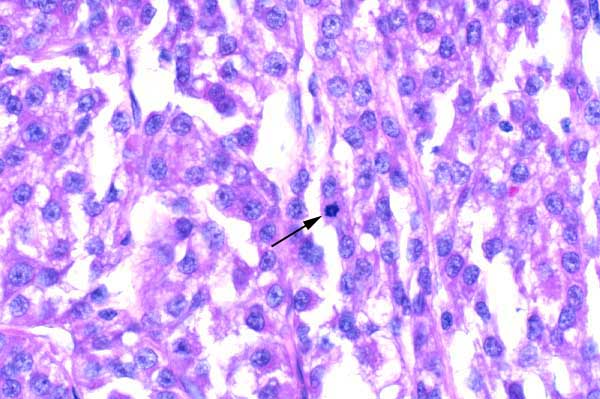

| 40x   |   Hematoxylin and Eosin | ||||

Neoplastic cells are polygonal, with a moderate amount of eosinophilic to finely vacuolated cytoplasm. Nuclei are round, with finely stippled chromatin and a single nucleolus. Note the mitotic figure (arrow).